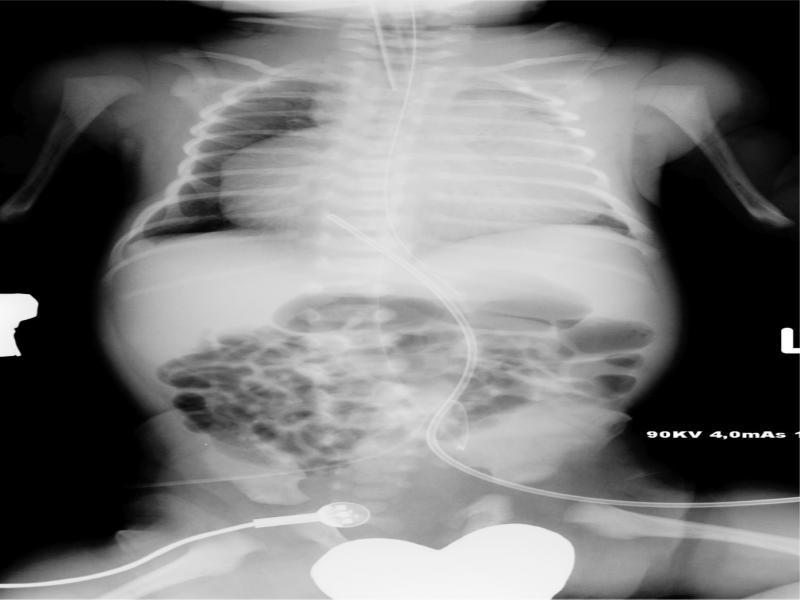

X-ray image from the neonatal ICU